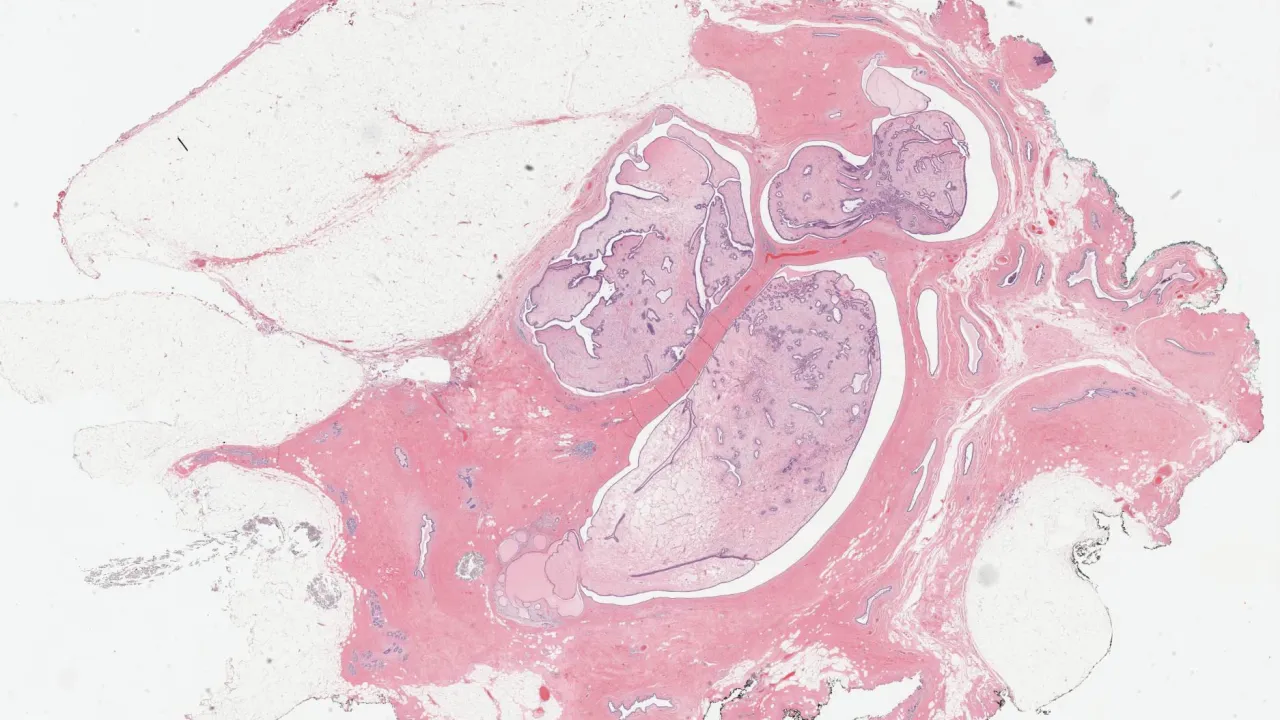

Testis, Mixed germ cell tumour, B-HCG stain

Testis, Mixed germ cell tumour, CD30 stain

Testis, Mixed germ cell tumour, Glypican stain

Testis, Mixed germ cell tumour, H&E stain